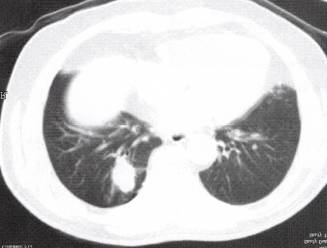

五、肺真菌病

如肺隐球菌病、组织胞浆菌病、球孢子菌病等(图10、图11),部分可表现为不规则肺部球形病灶,分叶状,酷似周围型肺癌,其病理基础为增生性肉芽肿性炎症,可伴有纤维组织增生。一般无钙化。多数鉴别需病理。